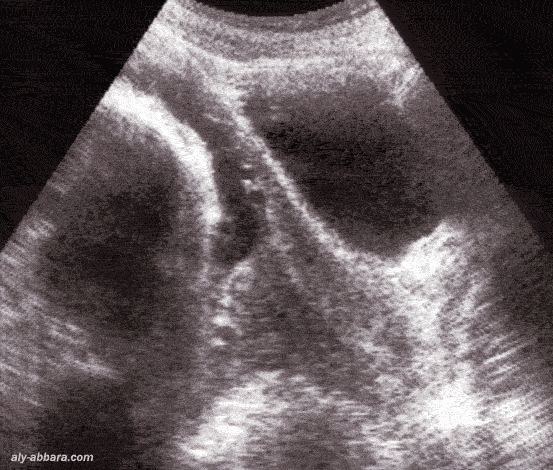

Procubitus du cordon ombilical fœtal

C'est une descente anormale du cordon ombilical en avant de la présentation

fœtale, alors que les membranes (la poche des eaux) sont encore intactes

• Si la rupture des membranes survient en la présence d'un procubitus du cordon, alors la complication inévitable est celle de la procidence du cordon :

• descente anormale, après ouverture de œuf, du cordon ombilical en avant de la présentation fœtale.

• Dans ce cas-là on peut trouver le cordon ombilical au niveau du pôle inférieur de la cavité utérine ou au niveau du canal cervical, voire dans le vagin ou hors des organes génitaux externes

• Le risque majeur c'est la compression du cordon qui entraîne inévitablement une hypoxie fœtale aiguë grave.